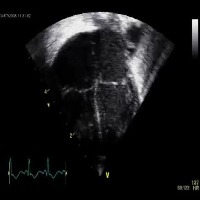

Healthcare and Medical Diagnostics: Utilize the "opt_subopt" model to analyze and categorize ultrasound images, helping medical professionals identify normal, abnormal, and suboptimal cases for better diagnosis and treatment planning.

Medical Education and Training: Integrate the computer vision model into medical education software and simulation tools, enabling students and healthcare practitioners to improve their skills in identifying and understanding different A4C classes in ultrasound images.

Quality Assurance for Ultrasound Equipment: Employ the "opt_subopt" model to evaluate the performance of ultrasound devices by identifying images with A4CSuboptimal and A4CAbnormal results, providing feedback to manufacturers for device improvements and maintenance.

Ultrasound Image Curation and Database Management: Implement the computer vision model in organizing large collections of ultrasound images based on their A4C classes, aiding researchers in finding specific categories of images more efficiently for their studies.

Telemedicine and Remote Consultations: Integrate the "opt_subopt" model with telemedicine platforms, allowing healthcare providers to review and analyze ultrasound images remotely and offer guidance to frontline staff in real-time based on the identified A4C classes.